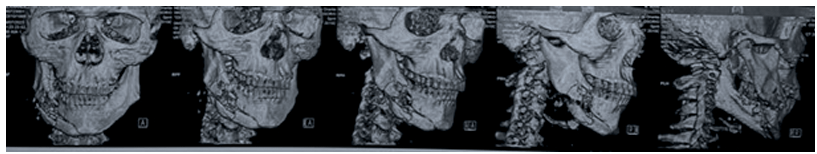

El diagnóstico radiológico fue mediante tomografía computarizada:

Tratamiento:

Para la elección de la actitud terapéutica se deben considerar varios aspectos, tales como experiencia, disponibilidad de medios, extensión de la lesión y estado de salud general. En el caso de heridas por proyectil balístico, es fundamental la obtención de imágenes; en este caso el gold stándar es la Tomografía Computarizada (TC) de Macizo facial y cuello si amerita. Por lo general, el momento ideal es previo a la reconstrucción de tejidos blandos, y dadas las circunstancias en que la vía aérea no estaba comprometida.